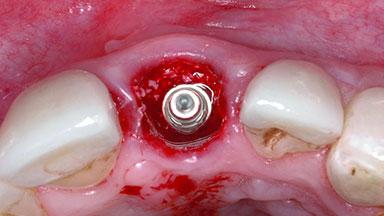

Replacement of a Failing Upper Left Central Incisor: Immediate Placement of an RC Bone Level Implant and Provisionalization

Placement Protocol Immediate implant placement

Tooth Site Maxillary incisor or canine

Socket Morphology Single-root socket

Socket Integrity Damage to one or more bone walls

Bone Volume Damage to one or more socket walls